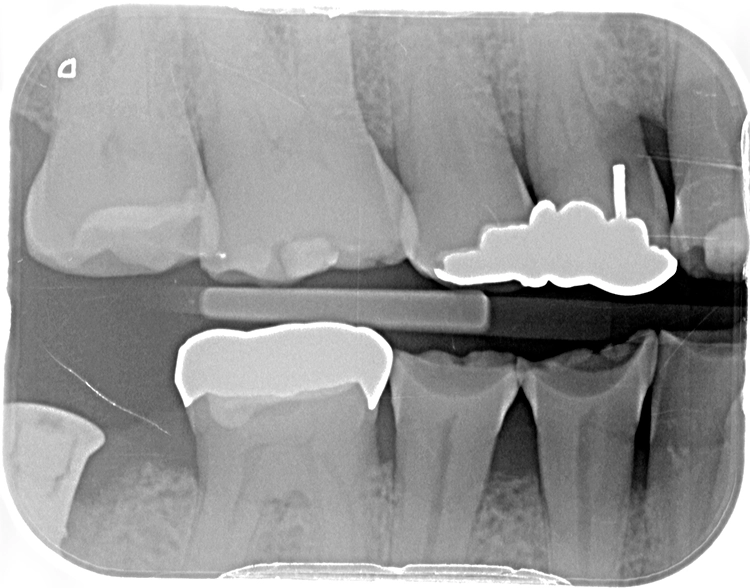

Die OPT-Aufnahmen zeigen keinen Anhalt auf nicht zahnverursachte Prozesse, dafür einen leichten bis mäßigen horizontalen und vertikalen Knochenabbau im Oberkieferseitenzahnbereich und generalisiert im Unterkiefer sowie einen periimplantären Knochenabbau in Regio 47 (Abb. 2). Die Zahnhartsubstanzdefekte imponieren als halbmondförmige Aufhellungen im Okklusalbereich von den Zähnen 37, 35, 34, 44 und 45. Es zeigen sich ebenso Aufhellungen im Approximalbereich mesial 24, distal 43 und mesial 37 (Abb. 4 und 5).

Egger/Wermuth/GrevenRote Ästhetik: Im Ober- und Unterkiefer zeigten sich generalisiert ausgedehnte Rezessionen mit bis zu 8 mm Attachmentverlust vor allem im Bereich der Eckzähne (Miller-Klasse III; Rezessionstyp [RT] 2 [69]. Das Band an keratinisierter Schleimhaut ist durchgehend vorhanden. Die Breite variiert im Eckzahnbereich von 1 mm bis zu 2 mm im Bereich der Unterkieferfrontzähne, der Prämolaren und Molaren (Abb. 1). Die fazialen Rezessionen sind mit approximalem röntgenologischem Attachmentverlust im koronalen Wurzeldrittel (Abb. 2) und Papillenverlust im Bereich zwischen den Kontaktpunkten und der approximalen Schmelz-Zement-Grenze assoziiert (Abb. 1). Der Patient verfügt über eine schmal geformte Oberlippe. Die Lachlinie verläuft mittelhoch (Abb. 3).